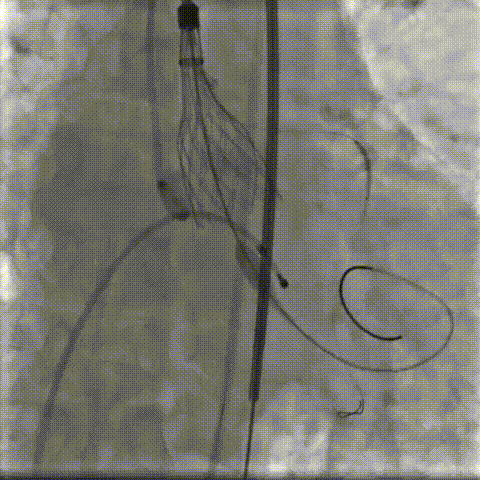

瓣环下精准定位稳定释放,瓣膜工作位造影考虑瓣叶推挤LCA阻挡临界状态,释放“烟囱支架”。

瓣膜稳定脱钩,20mm球囊后扩,“烟囱支架”Kissing,后扩后支架形态改善。